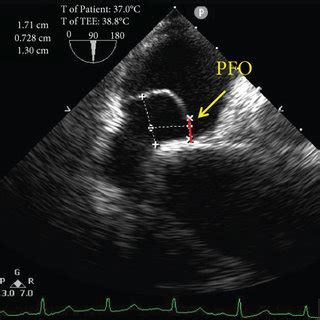

2408×2614

cvcasejournal.com

Three-dimensional Transesophageal Echocardio…